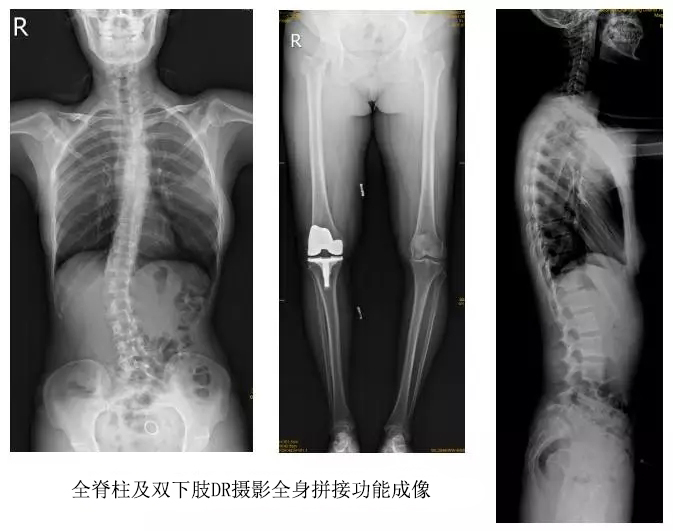

以某院所攝X光片為例,對比傳統(tǒng)攝片與全身拼接功能的區(qū)別:

傳統(tǒng)X光片只能觀察每個部位的局部情況,無法在統(tǒng)一體上進行連續(xù)、全面的觀察,全脊柱及下肢全長片則能直觀的看到整體形變。通過DR全身拼接功能實現(xiàn)的完整成像,為診治脊柱及下肢畸形提供了完美的臨床影像依據(jù),對臨床診斷、術前手術方案的制定和術后療效的評估等臨床應用具有十分重要的意義,有效滿足了此類疾病臨床診斷和治療的要求。